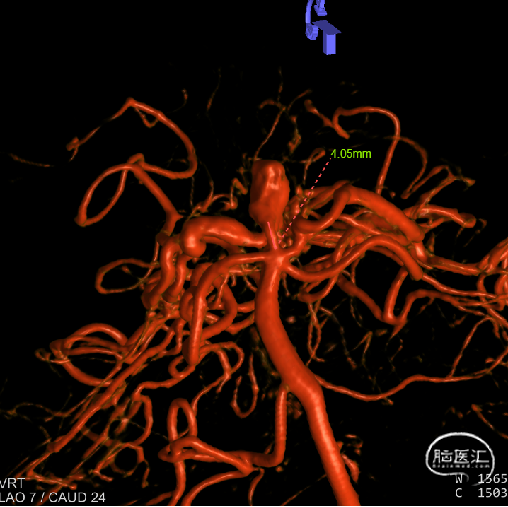

CT(CTA)检查提示:右颈内动脉C7段大小约3.6×3.8×3.6mm及基底动脉远端动脉瘤形成大小约9.7×7.6×9.3mm。

DSA:右侧P1段一6.8*9.7mm不规则囊状突起动脉瘤,远端P2段呈螺旋状蛇形动脉瘤改变。

右侧颈内3D

动脉瘤参数:

动脉瘤大小为6.8*9.7mm,瘤颈宽4mm

载瘤动脉(颈内动脉)近端狭窄处为1.7mm,近端末狭窄处为1.4mm,远端为2.4mm。